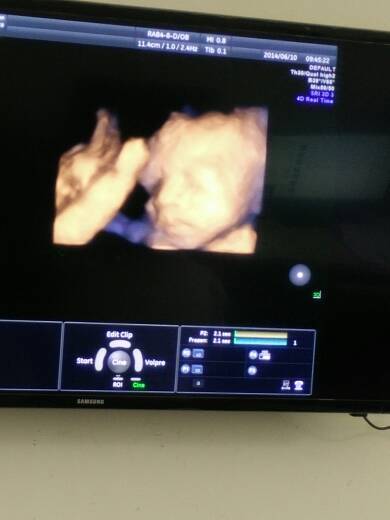

今天做四维了,宝宝真好看 今天做四维了,宝宝真好看 点击展开 岳夫人。 2014-06-10 10:46 为您推荐: 其他回答 :你好;这情况考虑是不会有伤害的,建议你不必担心的. 不要偏食。饮食尽可能广泛多样化。多吃高蛋白优质蛋白食物多吃蔬菜水果。不要喝酒咖啡。戒烟。 abc过眼烟云999 2014-06-10 10:58 相关问题 四维是什么,我的宝宝六个半月了可以做吗? 孕24+4天了 今天去做四维 宝宝有750g了 医生说偏小 是真的么?